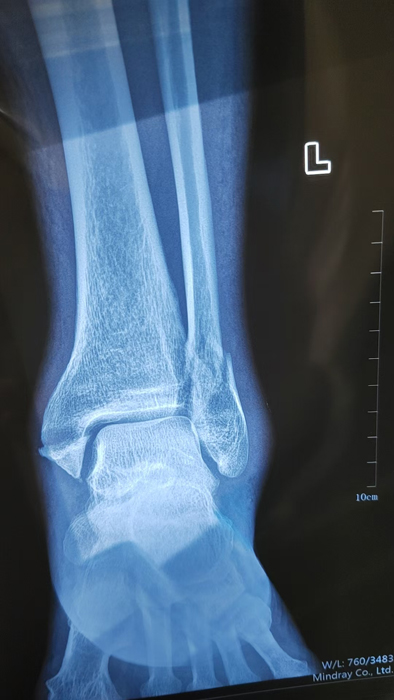

2月4日,何店鎮(zhèn)中心衛(wèi)生院接診一名左踝關(guān)節(jié)外傷患者,經(jīng)影像檢查,確診為左脛、腓骨下段骨折。外科醫(yī)生姜穩(wěn)迅速完成術(shù)前檢查及病情評估,并與患者及家屬深入溝通治療方案。在患者強烈要求于本院進行手術(shù)的情況下,為最大限度保障手術(shù)質(zhì)量與安全,該院特邀請醫(yī)共體牽頭單位——曾都區(qū)人民醫(yī)院脊柱創(chuàng)傷外科專家團隊前來指導(dǎo)。

本次幫扶由曾都區(qū)人民醫(yī)院脊柱創(chuàng)傷神經(jīng)外科主任徐三軍帶隊,專家團隊抵達后立即完成手術(shù)風險評估及術(shù)前準備。手術(shù)過程中,徐三軍主任嚴格規(guī)范完成各項手術(shù)操作,并同步結(jié)合手術(shù)步驟,為該院外科醫(yī)師詳細講解骨折手術(shù)的關(guān)鍵要點、操作技巧、術(shù)中注意事項及術(shù)后康復(fù)要領(lǐng)。通過“手把手”的實戰(zhàn)帶教,專家將豐富的手術(shù)經(jīng)驗與規(guī)范的診療思路傾囊相授,讓該院醫(yī)護人員在實操中學(xué)習(xí),在過程中成長。